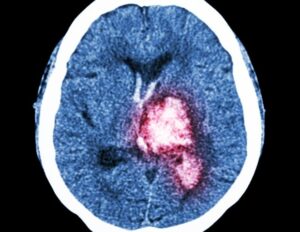

Η μητέρα περιέγραψε ότι κατέγραψε σε ένα βίντεο με τρία μέρη, τη φωτογραφία που απεικονίζει το μόνιτορ που απεικονίζει τους παλμούς οι οποίοι φτάνουν τους 165, με καλό οξυγόνο και μετά πέφτει στους 61 με μηδενικό σχεδόν οξυγόνο. Κατέγραφε μια το μόνιτορ και μια την κλινική εικόνα του παιδιού. Βάση των ισχυρισμών της έχει ενημερώσει και την αστυνομία. Ο γιατρός λέει ότι δεν το έχει στα χέρια του.

“Είναι ένα ντοκουμέντο που δείχνει την πτώση με οξυγόνο, υπάρχει και ένα άλλο βίντεο που δείχνει τους σπασμούς και είναι σοκαριστικό, δεν είναι για τον “αέρα” αλλά για τις αρχές”, είπε η Αγγελική Νικολούλη.